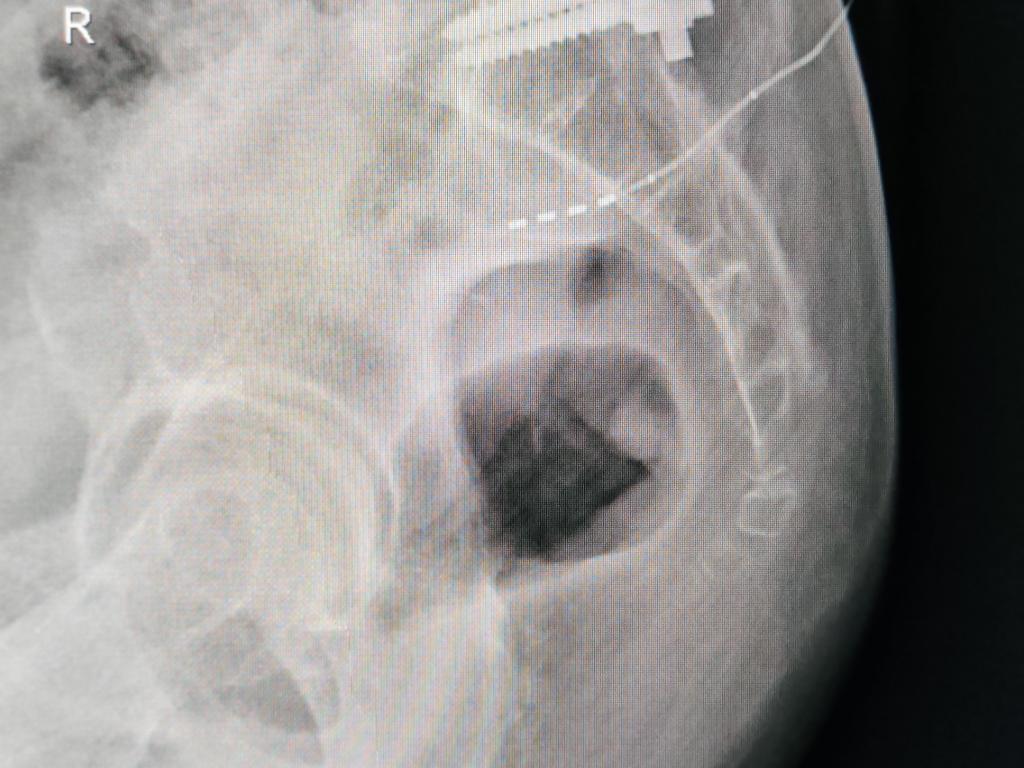

经术中超声辅助定位、术中测试,确认患者双侧S3神经感觉与运动应答均较差,左侧S2测试患者获得了“左侧臀部、大腿根部及肛门周边感觉良好应答、左侧足底跖屈反射刺激应答明确且无腓肠肌震颤、在增加脉宽后会阴部左侧区域感觉应答明确”,依据西安交大二附院“尿控与盆底修复”诊疗团队在完全脱离X线-B超辅助定位骶神经调控疗法个体化手术经验,术中确定选择患者左侧S2神经孔置入电极并确认深度并精准释放,术中最低测试电压0.5V,等待患者术后体验治疗24小时、完成X线电极定位复查,开始骶神经调控Stage1体验治疗。

临时刺激器连接并开机 SNM Stage1术中24小时X线复查